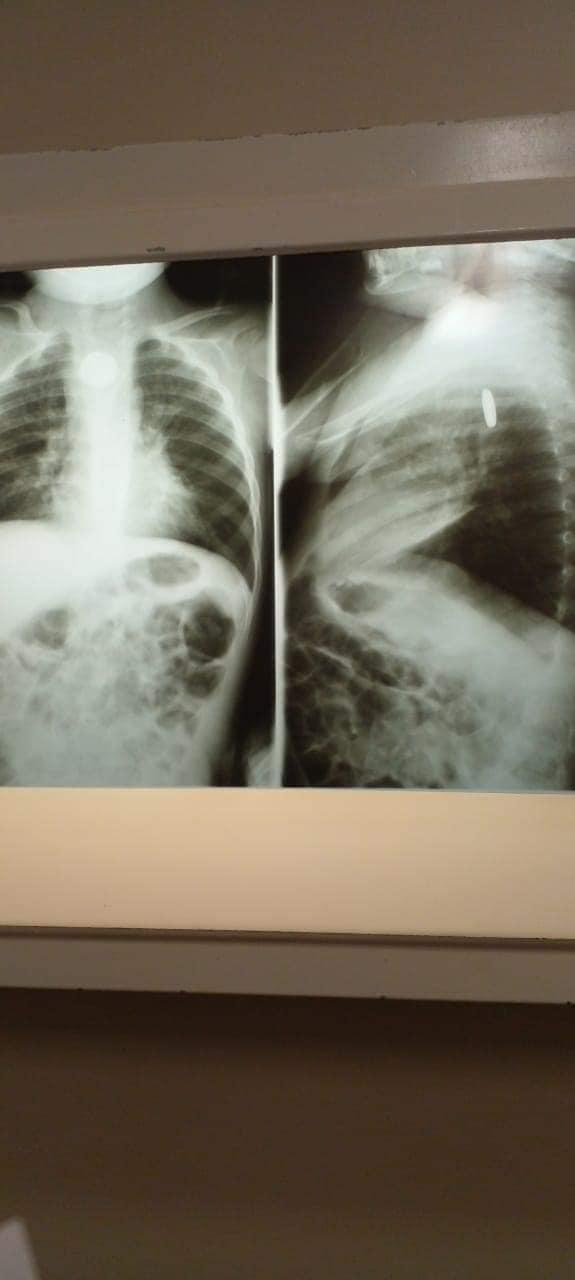

Copil de 2 ani, în stare critică după ce a înghiţit o baterie | Sursa foto: Facebook / Jesús Olivarria